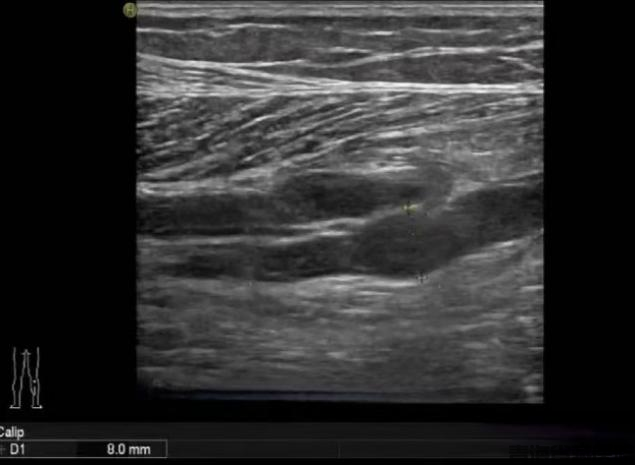

图片3.png

图片4.png

常规二维灰阶超声检查

小腿肌间静脉管腔扩张,充满低回声,探头加压无法压扁,提示血栓形成